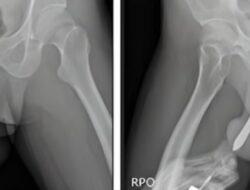

Kisah Tragis, Pria Indonesia Alami Cedera Serius Akibat Tindakan Seksual Berbahaya

Sebuah kejadian mengejutkan melibatkan seorang pria berusia 43 tahun dari Indonesia telah menciptakan gelombang kehebohan….